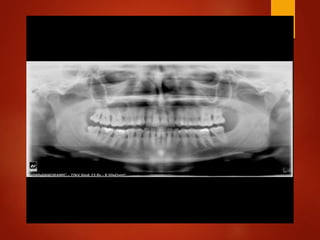

El documento es un registro médico odontológico que muestra las fechas de las visitas de un paciente al centro de salud El Raval, incluyendo exámenes y tratamientos realizados como la extracción de cálculos salivales en abril y mayo de 2012.